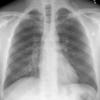

Normal PA Male

Date: 12/06/2014

Views: 6326